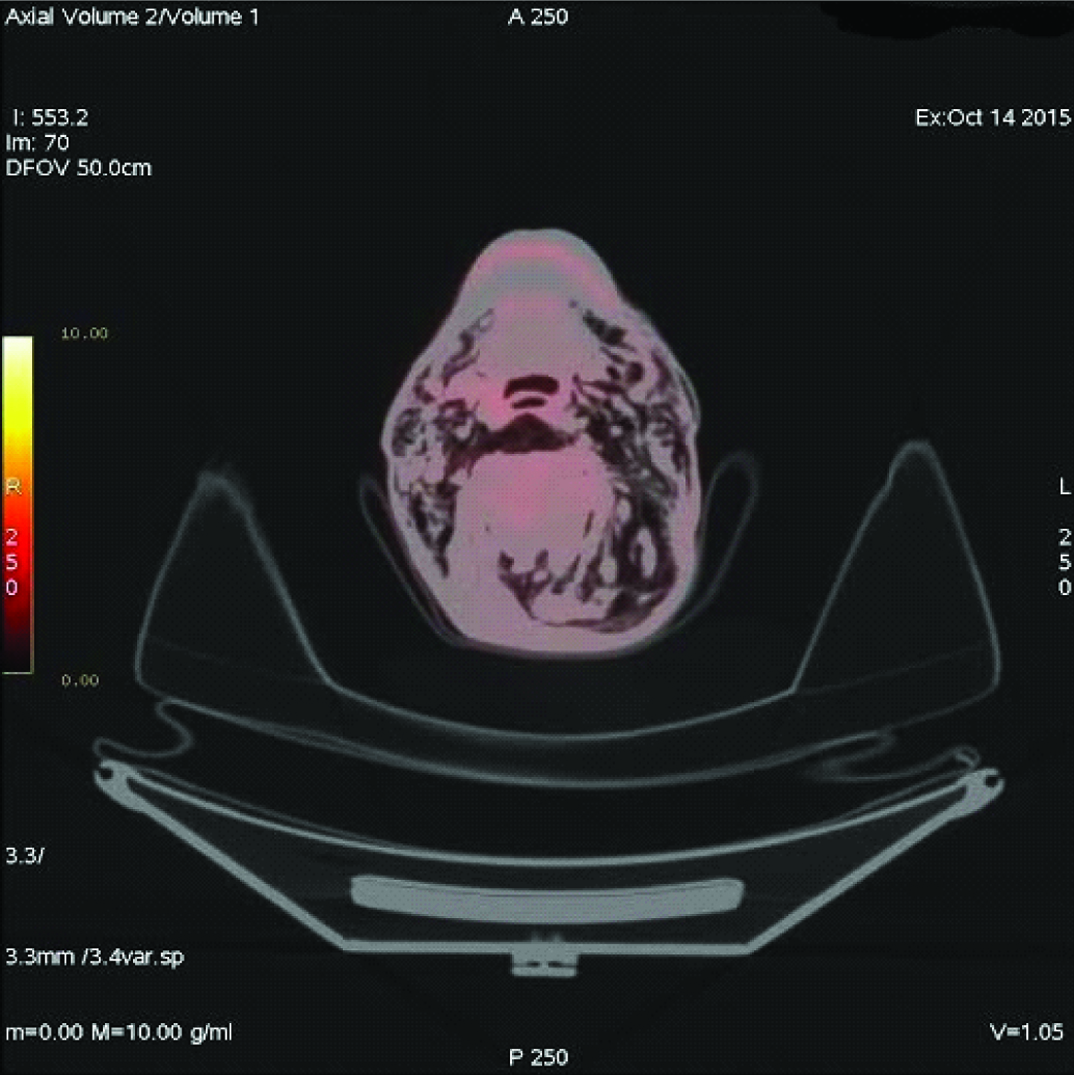

A 69-year-old male patient complained of dyspnoea, cough, and fatigue since one month. On physical examination respiratory rate was 26/minute, blood pressure 140/85mmHg and pulse rate 82/minute. Percussion determined submatity in the middle lobe of the left hemi-thorax on auscultation. In the chest radiography [Table/Fig-1], there was a space-occupying lesion in the left hilus. Spirometry results were Force Expiratory Volume 1= 69, and Force Expiratory Volume 1/Force Vital Capacity = 95. A non-contrasted CT thorax was performed one day later, it was observed that a mass with 8.9 cm diameter was located in the left hilus of the lung, and a minimal pneumothorax was determined at the inferolateral part of left hemithorax. The patient refused bronchoscopic biopsy so transthoracic biopsy was performed. After transthoracic biopsy, broncoscopy was performed. The histopathologic report confirmed it as squamous cell carcinoma. Four days after the transthoracic biopsy, swelling started in the posterior part of the body and expanded progressively. After seven days of biopsy, Positron Emission Tomography/Computed Tomography imaging was done for staging of primary mass, which detected necrosis in the middle of tumour [Table/Fig-2]. It also revealed, minimal pneumothorax in the left hemithoraces and massive subcutaneous emphysema extended in bilateral neck region [Table/Fig-3], left side of the body and it sprawled up to L4 vertebral level in the left side. So, final diagnosis was lung cancer and transthoracic biopsy related massive SE. Patient refused for the lung cancer treatment and died three months after the diagnosis.

Emphysema in bilateral subcutaneous neck tissue.